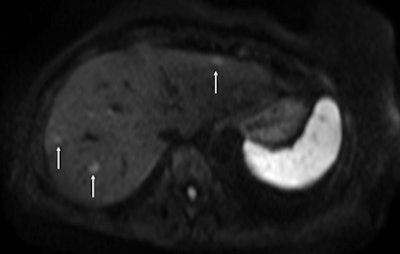

Above: Fat-suppressed T2-weighted fast spin-echo MR image obtained in a 61-year-old man with liver metastases from colorectal cancer. Only one metastasis in the right liver lobe is seen here (arrow). Moreover, this lesion is barely seen because it is located next to the vessel. Below: On the diffusion-weighted image, the same lesion is seen, as well as two additional metastases: one in the right liver and one in the left liver. All metastases are strongly hyperintense compared with the background liver at b = 600 sec/mm2, indicating restricted diffusion. All these lesions were surgically confirmed as metastases. Images courtesy of Dr. Valérie Vilgrain.

"Four years ago, intraoperative ultrasound sometimes revealed new lesions that had been missed in scans for staging colorectal liver metastasis. Now with diffusion-weighted MRI and the use of hepato-specific MR contrast agents, this is very unlikely to happen," she said, pointing to further details about surgical indications and candidates' prognostic factors to be provided by Dr. Jacques Belghiti, head of the department of hepatobiliary surgery, at the same Paris hospital.